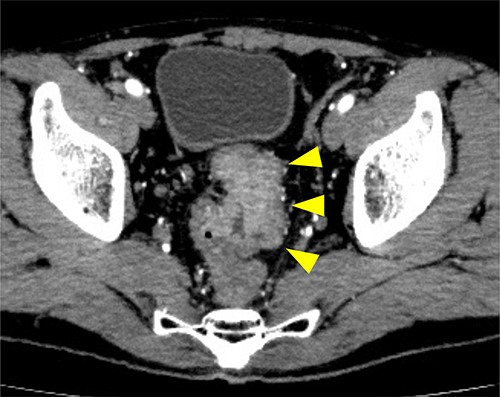

Subsequently, we performed transrectal drainage of the abscess in the lithotomy position without endoscopy. After the incision of the excluded rectal mucosa at 7 cm from the anal verge by the electric scalpel and penetration of the abscess wall by the Kelly clamp, a massive purulent discharge was observed. Next, a transanal rectal drainage tube (MIT drain®, effective length 12 cm; Create Medic Co., Ltd, Yokohama, Japan) was inserted into the abscess cavity without the use of a guide wire, and saline irrigation was performed. After transrectal drainage, the patient’s pain and inflammatory laboratory findings improved rapidly. Pelvic CT showed shrinkage of the cavity 3 days after the drainage (Fig. 3). Bacterial culture test and cytology of the drainage contents revealed negative growth and no malignancy, respectively. The biopsy results showed moderately differentiated tubular adenocarcinoma. The inserted tube was removed on the seventh day after the drainage, and the patient was discharged on the eighth day. In the outpatient department, total colonoscopy revealed that the exclusion from outside the rectal wall on the anal side of the tumor diminished, and the incised mucosa healed as a scar. Ink sticks were marked near the scar on behalf of the combined resection of the tumor. Pelvic CT revealed that the pelvic abscess had disappeared 1 month after drainage (Fig. 4).

Pelvic CT performed 3 days after drainage in the sagittal section. Abscess cavity remarkably shrunk (arrowheads).